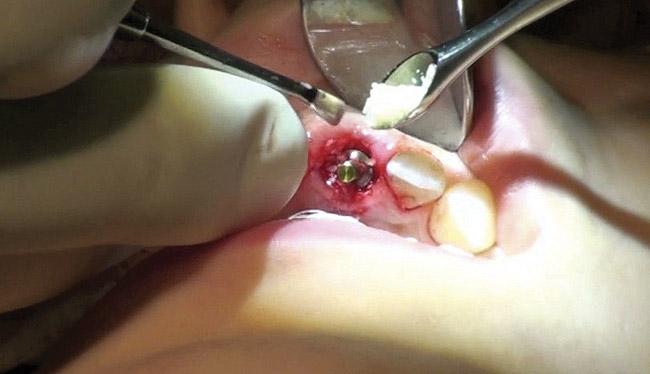

Figure 13  Initial osteotomy preparation with 2.1-mm precision drill, site No. 9. Priority level: 3.

Figure 13

The osteotomy was started slightly palatally in alignment with the surgical guide, using a 2.1-mm precision drill (Figure 13) and finalized with shaping drills under copious external irrigation with sterile water. Special attention was paid to overcorrecting the osteotomy preparation toward the palate, where the bone is denser. An implant in this area—especially a tapered implant, as was used here—will usually veer toward the facial surface during insertion. Using the surgical guide to superimpose the central axis of the implant on the previous location of the central incisor’s cingulum facilitates accurate positioning (Figure 14).

The periodontist positioned a 4.3-mm x 16-mm regular-platform implant flush with the facial crest and 1 mm subcrestally interproximally (Figure 15), with a manually driven final seating torque value > 50 Ncm, followed by hand-tightened attachment of the immediate temporary abutment.